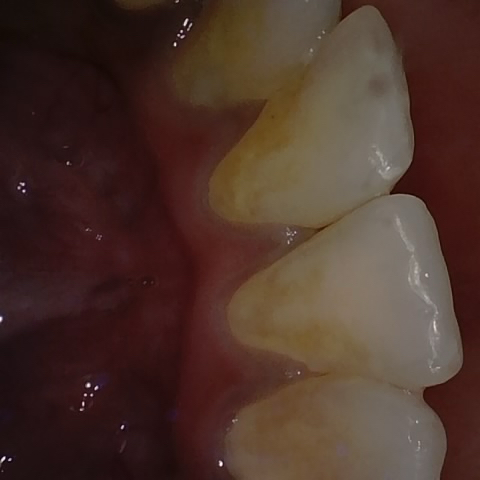

Annotated as "Good"